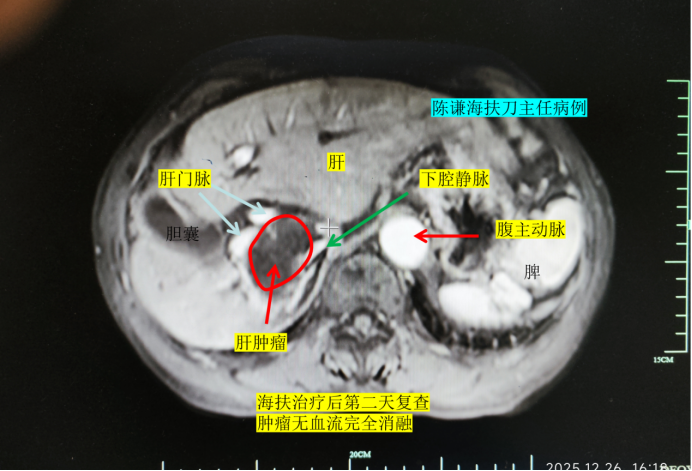

幸运的是,手术过程十分顺利,术中消融效果达到预期。术后复查增强磁共振显示,病灶实现消融满意,门静脉、下腔静脉、肝静脉等重要血管均未受损伤,老人术后第二天便顺利出院,恢复情况超出预期。